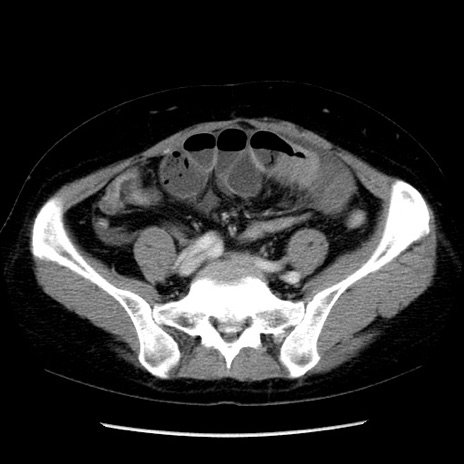

症例6(横断像)

【症例】50歳代女性

【主訴】下腹部痛

【現病歴】本日朝より下痢2回あり。 昼食を食べた後、嘔吐3回、下腹部痛認め、症状軽快せず、当院救急搬送。

最終食事:本日昼(生ものなし)。 昨日の夜、刺身を食ぺたとのこと。周囲に同様の症状の者なし。普段、排便は毎日あるとのこと。

【既往歴】卵巣癌術後(8年前に当院で卵巣摘出)

【身体所見】 意識清明、腹部:平坦、腸蠕動音→、やや硬、下腹部自発痛・圧痛あり、反跳痛あり、筋性防御なし。

【データ】WBC 16000、CRP 0.01